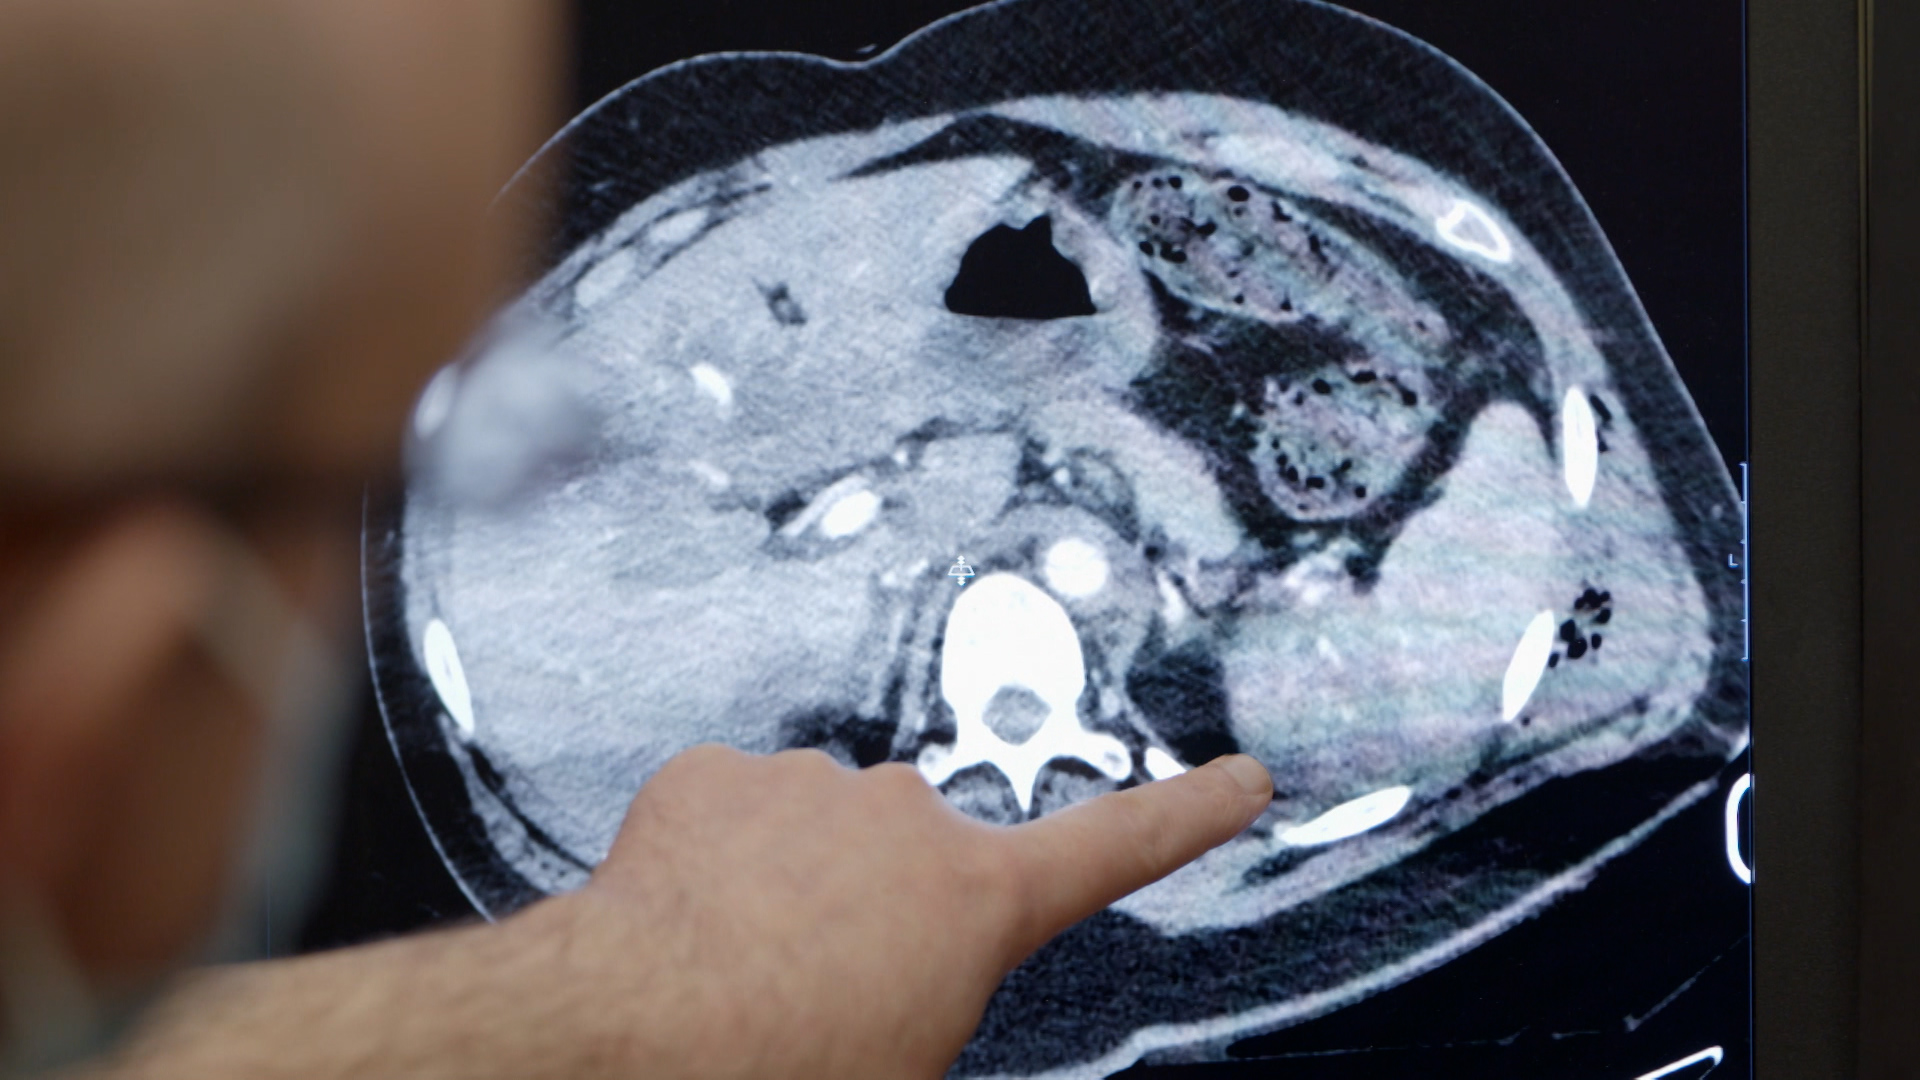

George Meynell, 66 anni, muore improvvisamente dopo un grave incidente stradale. Il medico legale indaga se le lesioni o altre cause naturali abbiano portato al decesso, svelando una storia di dolore, fragilità e un'eredità familiare di malattie cardiache.